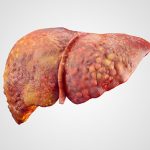

In a healthy individual the liver can repair itself when damage is done. When the liver is unable to repair damage it can result in liver failure. This impedes on the liver’s ability to perform its many functions and can reduce the health of an individual greatly.

In a healthy individual the liver can repair itself when damage is done. When the liver is unable to repair damage it can result in liver failure. This impedes on the liver’s ability to perform its many functions and can reduce the health of an individual greatly.

Liver failure can be life-threatening, so treatment should occur immediately. The cause of the liver failure is what will determine the mode of treatment. If liver failure is caused by an overdose of painkillers, that can be treated and often reversed. If liver failure is caused by a virus, treatment can better support the liver so it can heal itself.

Ultimately, if liver failure is severe then a transplant may be required.